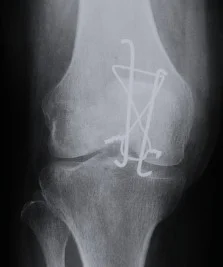

| Tension Band Wires | Special mechanics in – Patella – Olecranon – Malleolar fractures | ![]() |

| Screws | Good fixation – stable – Can apply good inter‑fragmentary compression In simple fractures Can be applied percutaneous | ![]() ![]() |